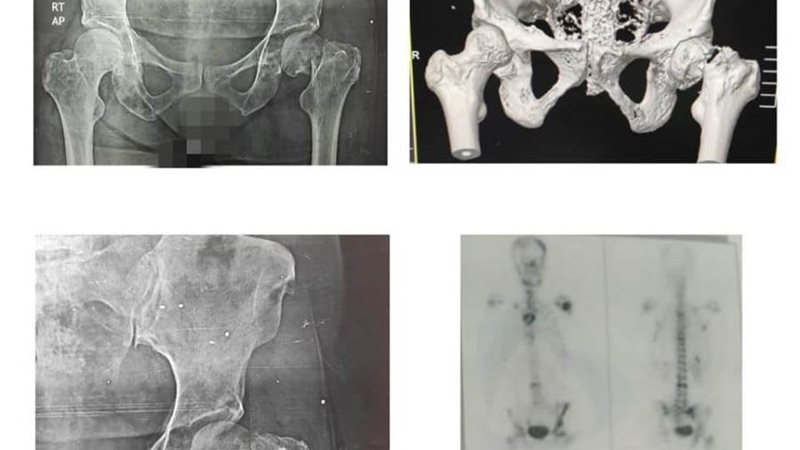

وأكد الدكتور تامر حمدى مدير عام المستشفى على إجراء جراحة عاجلة وخطيرة لمريضة تبلغ من العمر ٤٥ عامًا تعانى من ورم متقدم بالثدى وثانويات سرطانية عديده بالمخ والعمود الفقرى والجمجمة والقفص الصدرى والكتفين والفخذين وعظام الحوض .. أدت إلى كسر بعنق عظم الفخذ .. مما استدعى استبدال مفصل الفخذ بمفصل كامل أسمنتى ثلاثى الأقطاب.

وأضاف حمدى أن الجراحات فى مثل هذه الظروف من حيث انتشار الورم بالحق والفخذ تعد من أصعب الجراحات .. حيث تتسبب بنزيف حاد مستمر أثناء الجراحة وفقدان جزء كبير من الدم ووجود فجوات بالعظام .. مما يزيد صعوبة تركيب المفصل الصناعي ، وأن ما يزيد الأمور تعقيداً فى مثل هذه الحالات وجود هشاشة شديدة بالعظام .. مما قد يتسبب بكسور أثناء الجراحة.